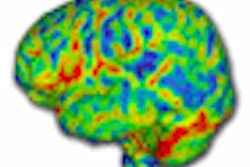

Because body tissues and intravascular iodine-based contrast media have unique spectral characteristics when exposed to different x-ray energy levels, DECT enables the mapping of iodine and, thus, blood distribution within the myocardium as a surrogate of myocardial perfusion and blood volume, they explained.

The DECT data were used to reconstruct anatomic coronary CT angiographic images and to map the myocardial iodine distribution within the left ventricular myocardium, Ruzsics and his team reported. Two readers working independently analyzed all the DECT studies for stenosis and myocardial iodine defects.

Rather, the technique exploits the material differentiation capabilities of cardiac dual-source CT in dual-energy mode to delineate myocardial areas with decreased contrast and, hence, blood, they content.